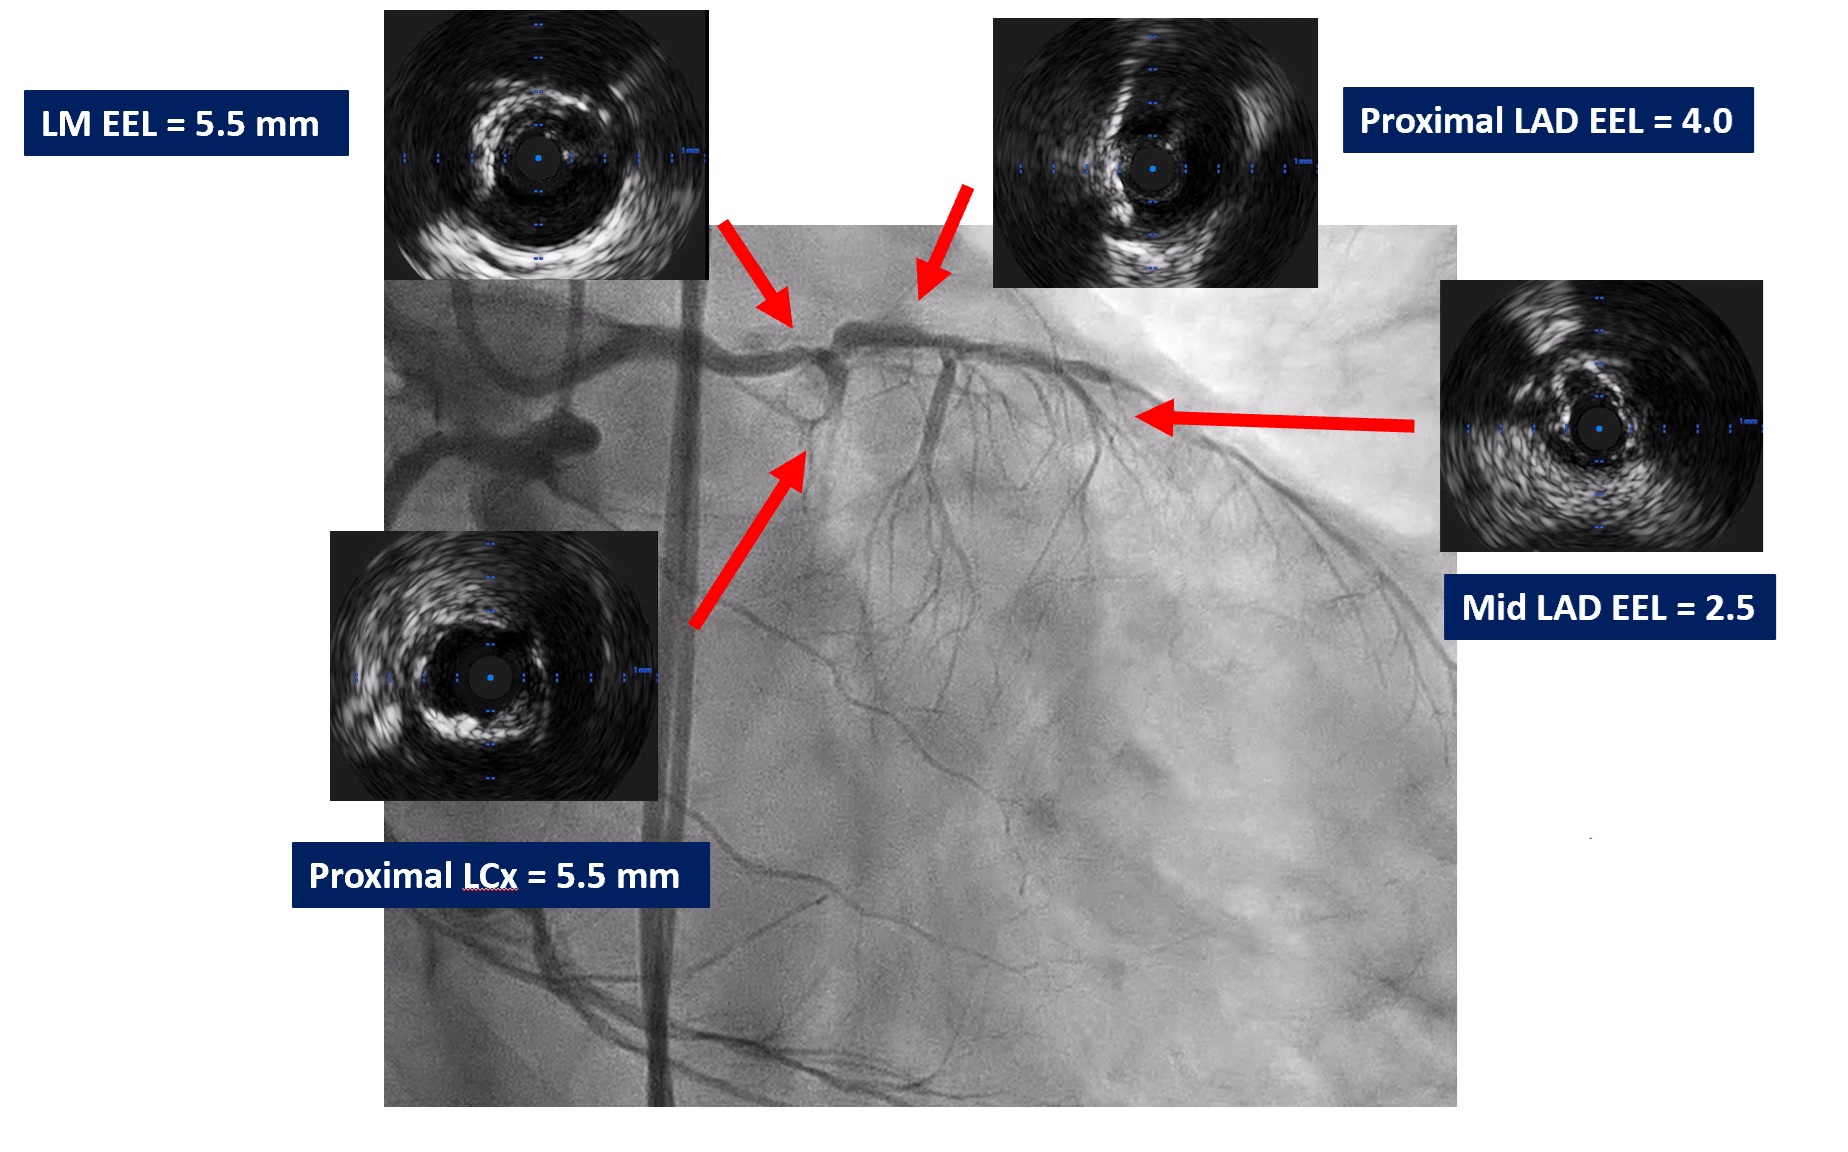

Coronary angiography revealed heavily calcified along LM, proximal to mid LAD, LCx and proximal RCA. 50% stenosis at distal LM bifurcation (Medina 1-1-0). 70% stenosis at proximal LAD and total occlusion at mid LAD. Total occlusion at proximal LCx. No significant stenosis of RCA. There were collateral circulations from septal branch of LAD to distal LAD and from PL to distal LAD and distal LCx.

We performed PCI at CTO LAD and LCx with contralateral injection with antegrade wiring and upfront rotablation at LM, LAD and LCx due to heavily calcified lesion. The 7 Fr EBU 3.5 and 6 Fr JR 4.0 catheter were engaged into LCA and RCA, respectively. We opened the LCx CTO segment using microcatheter with Fielder XT guidewire (GW) then rewire from LCx to distal LAD. The CTO GW was exchange to RotaWire Floppy. Rotablation was done at LM-mid LAD with Burr 1.5 mm and LM-proximal LCx with Burr 1.5 mm. IVUS showed EEL of mid LAD = 2.5 mm, proximal LAD = 4.0 mm, distal LM = 5.5 mm and proximal LCx = 3.5 mm. The lesion of mid LAD was prepared with scoring balloon 2.0/15 mm and LM-proximal LAD with scoring balloon 3.5/15 mm. A 2.5/33 mm stent was deployed from proximal-mid LAD. We decided to stenting the lesion at proximal LCx before stenting the lesion at LM-proximal LAD using provisional one stent and POT-kiss-POT technique. A 3.0/26 mm stent was deployed at proximal LCx. A 3.5/38 mm stent was deployed from distal LM-proximal LAD and 3.5/13 mm stent from ostial LM-distal LM. POT was done with a non-compliance (NC) 5.0/12 mm balloon along LM stent. Kissing balloon inflation with NC 3.0/15 mm balloon at LM-LCx and 3.5/15 mm balloon at LM-LAD then final POT with NC 5.0/12 mm was done. IVUS showed well stent expansion, no malapposition and no stent edge dissection. The patient had no re-admission. Echocardiography after 3 months showed significant improvement of LV function to 56%.